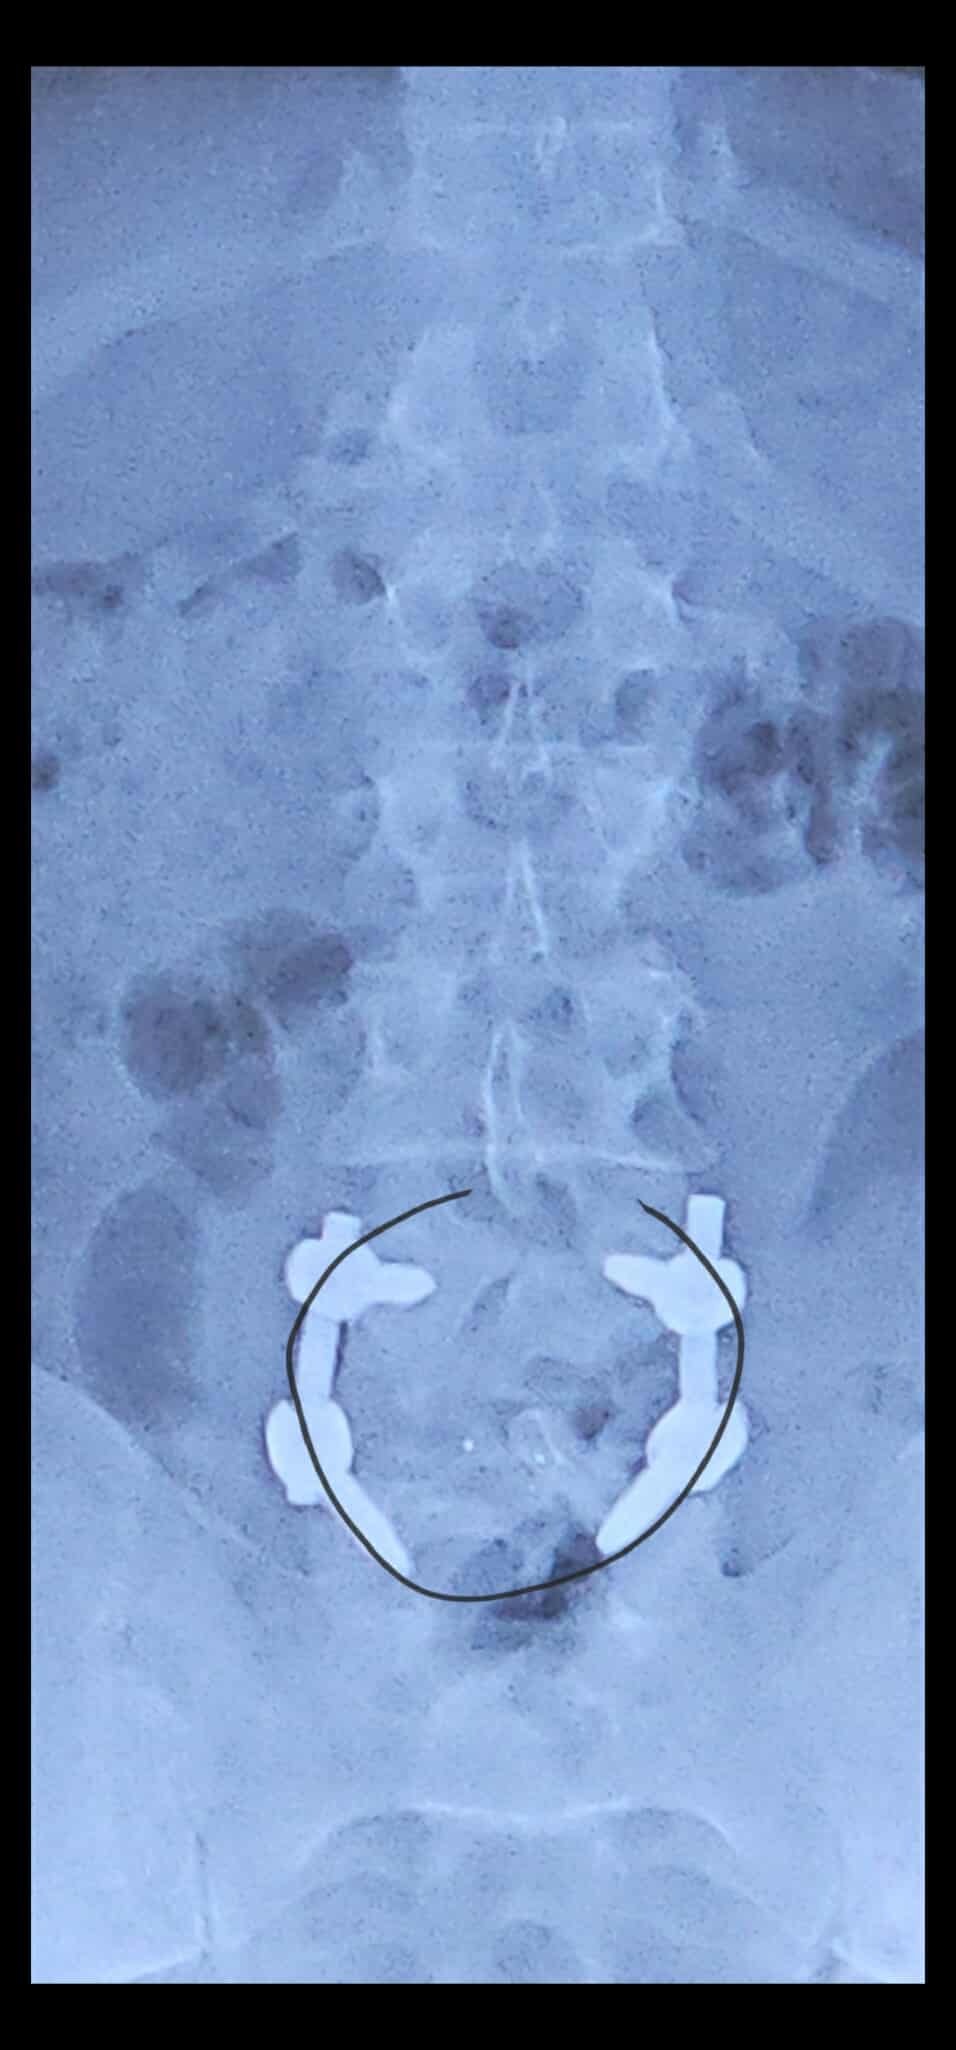

My name is Sonny Gentry. I was in a wreck 3 years ago at no fault of my own at 70 mph. As time passed by, my neck and lower back began to deteriorate. After waiting a very long time, I finally had surgery on July 15th, 2024, and that was a complete fail. I am only able to stand for 30 minutes at a time, and meds only help very little. Just really needing help with bills and meds as I am unable to work after all these years of working. Please feel in your heart to help. If CashApp $southerneuf81 or Venmo @sonny-gentry25 is better for you, then that's great too.